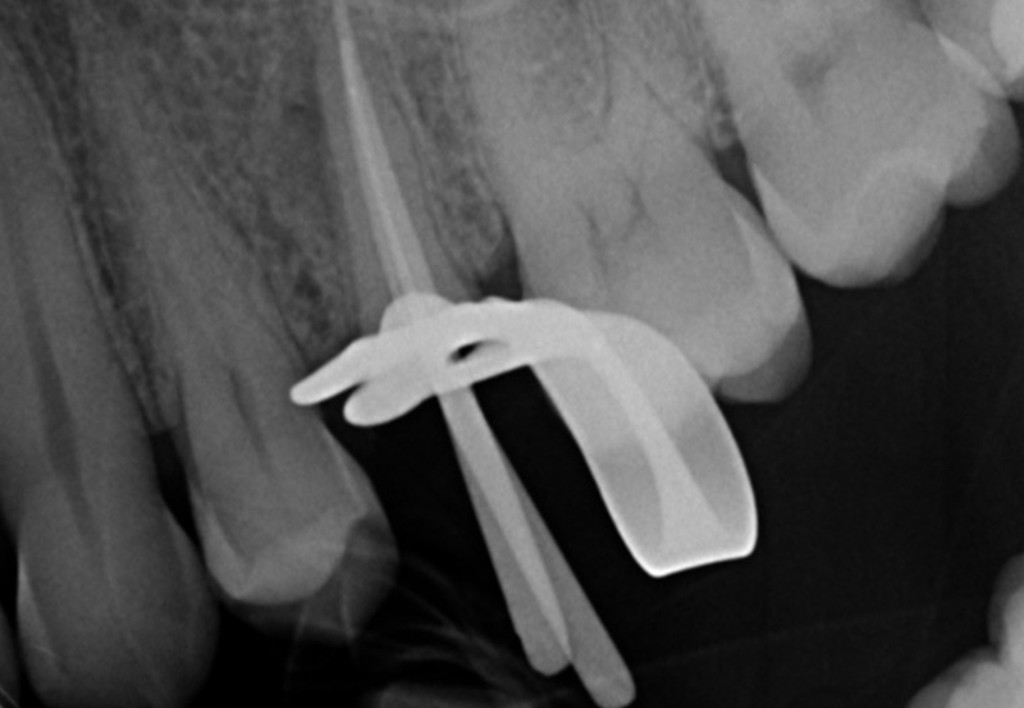

Galleria fotografica